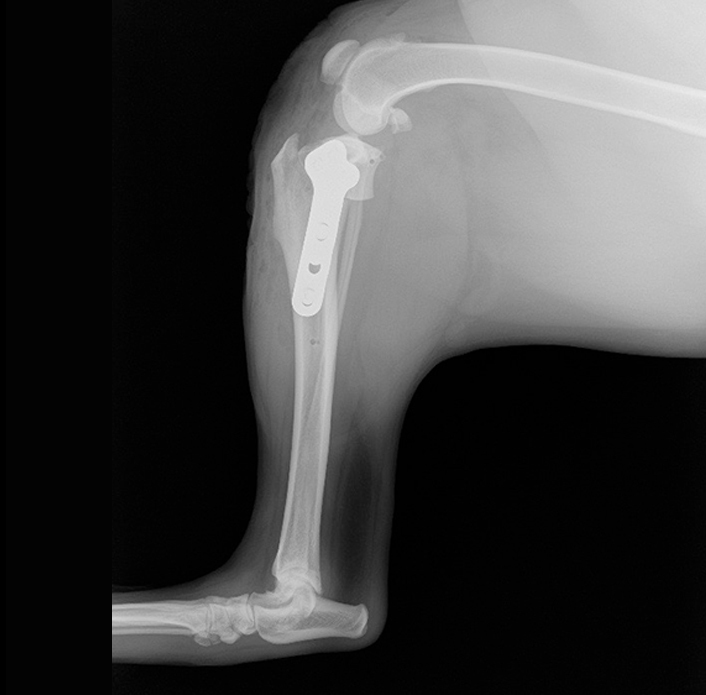

整形外科

まずは、「丁寧に触ること = 触診」 をして、痛みの部位を特定していきます。

レントゲン検査はしっかりと撮影します。

検査に麻酔は必要ありません。動物に負担のない検査です。

手術が本当に必要かどうか、どの手術方法が良いのか様々なご提案をさせていただきます。